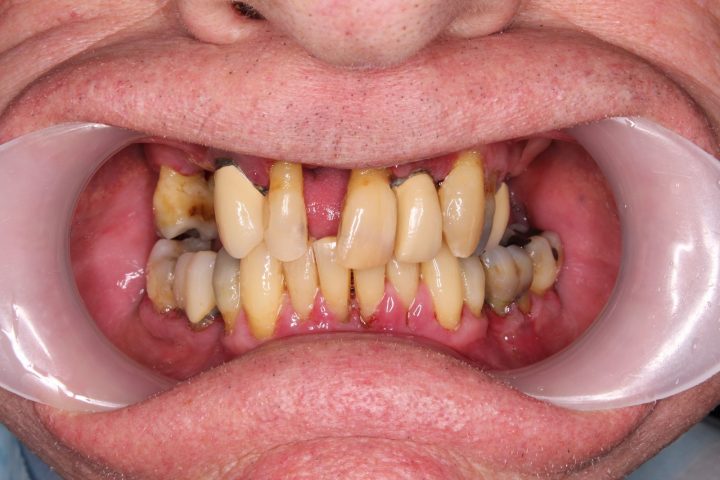

Daniel

Daniel ist ein 54-jähriger Lastwagenfahrer. Seit seiner Kindheit hatte er schlechte Zähne, bis er in die Klinik kam, alle fallen raus.

Aufgrund von der CT- Aufnahme haben wir mit dem Patienten zusammen entschieden, dass wir 4-4 Alpha Bio Implantate in Ober- und Unterkiefer einsetzen.

Die Operation dauert zweimal 1,5 Stunden lang, und wurde der provisorische Zahnersatz im Ablauf den 5 Tagen fertig. Nach der 3 Monate langen Heilungszeit wurden zwei Stegprothesen auf 4-4 Implantate befestigt.

Die Implantatprothese sichert die Stabilität für den Patienten, so konnte Daniel am Ende der Behandlung wieder Steak essen, was sein Traum war.